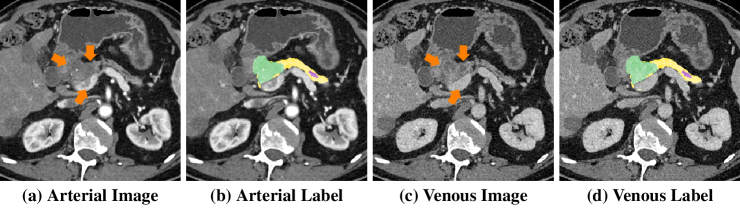

Refer to caption

Figure 3: Qualitative comparison of different methods, where HPN enhances PDAC mass segmentation (green) significantly compared with other methods. (Best viewed in color)

We can observe additional benefit of our HPN over hyperNet-aug (e.g., abnormal pancreas: 85.87%percent85.8785.87\% to 86.65%percent86.6586.65\%, PDAC mass: 61.69%percent61.6961.69\% to 63.94%percent63.9463.94\%, pancreatic duct: 54.07%percent54.0754.07\% to 56.77%percent56.7756.77\%, 3D-ResDSN). Overall, HPN observes an evident improvement compared with HyperNet, i.e., abnormal pancreas: 85.79%percent85.7985.79\% to 86.65%percent86.6586.65\%, PDAC mass: 61.69%percent61.6961.69\% to 63.94%percent63.9463.94\%, pancreatic duct: 54.07%percent54.0754.07\% to 56.77%percent56.7756.77\% (3D-ResDSN). The p-values for testing significant difference between hyperNet and our HPN of all 3 targets are p<0.0001𝑝0.0001p<0.0001, which suggests a general statistical improvement. We also show two qualitative examples in Fig. 3, where HPN shows much better segmentation accuracy especially for PDAC mass.